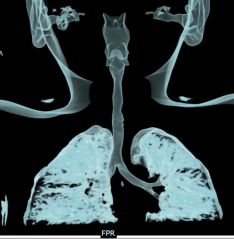

A 6-year-old female child presented to our clinic with progressive breathlessness and stridor for a duration of 5 days. She had a recent history of road traffic accident and sustained head injury and underwent craniotomy for extradural hemorrhage. Post-surgery she was on mechanical ventilator support for 10 days after which she was extubated. She developed stridor after 7 days of extubation. CT Neck revealed focal hour-glass configuration, concentric asymmetrical subglottic narrowing with associated soft tissue thickening 2-3cm below the level of vocal cords, with a diameter of 4.5 x 5.0 mm (AP X TR) at the point of maximal narrowing. Diagnostic flexible bronchoscopy showed circumferential stenosis (Grade III Myers-Cotton) of subglottic area about 2.5 cms below the glottis and we could not negotiate beyond the level of stenosis.

Rigid bronchoscopic repair of the stenosis was performed combining serial rigid bronchoscopic dilatations and balloon bronchoplasty using CRE dilatation balloons of varying sizes. Post dilatation, we were able to negotiate the rigid bronchoscope beyond the level of stenosis and were able to achieve a lumen of 100% with no residual stenosis. Follow-up CT Neck showed normal caliber of tracheal lumen with a luminal diameter of 8.6 x 8.3 mm at the level of previous narrowing. Total reduction of the clinical stridor was observed post procedure. Surveillance bronchoscopy after 4 weeks showed no further narrowing and good patency of tracheal lumen. Patient remained asymptomatic in subsequent follow up visits with improved pulmonary function tests

Radiology Images: